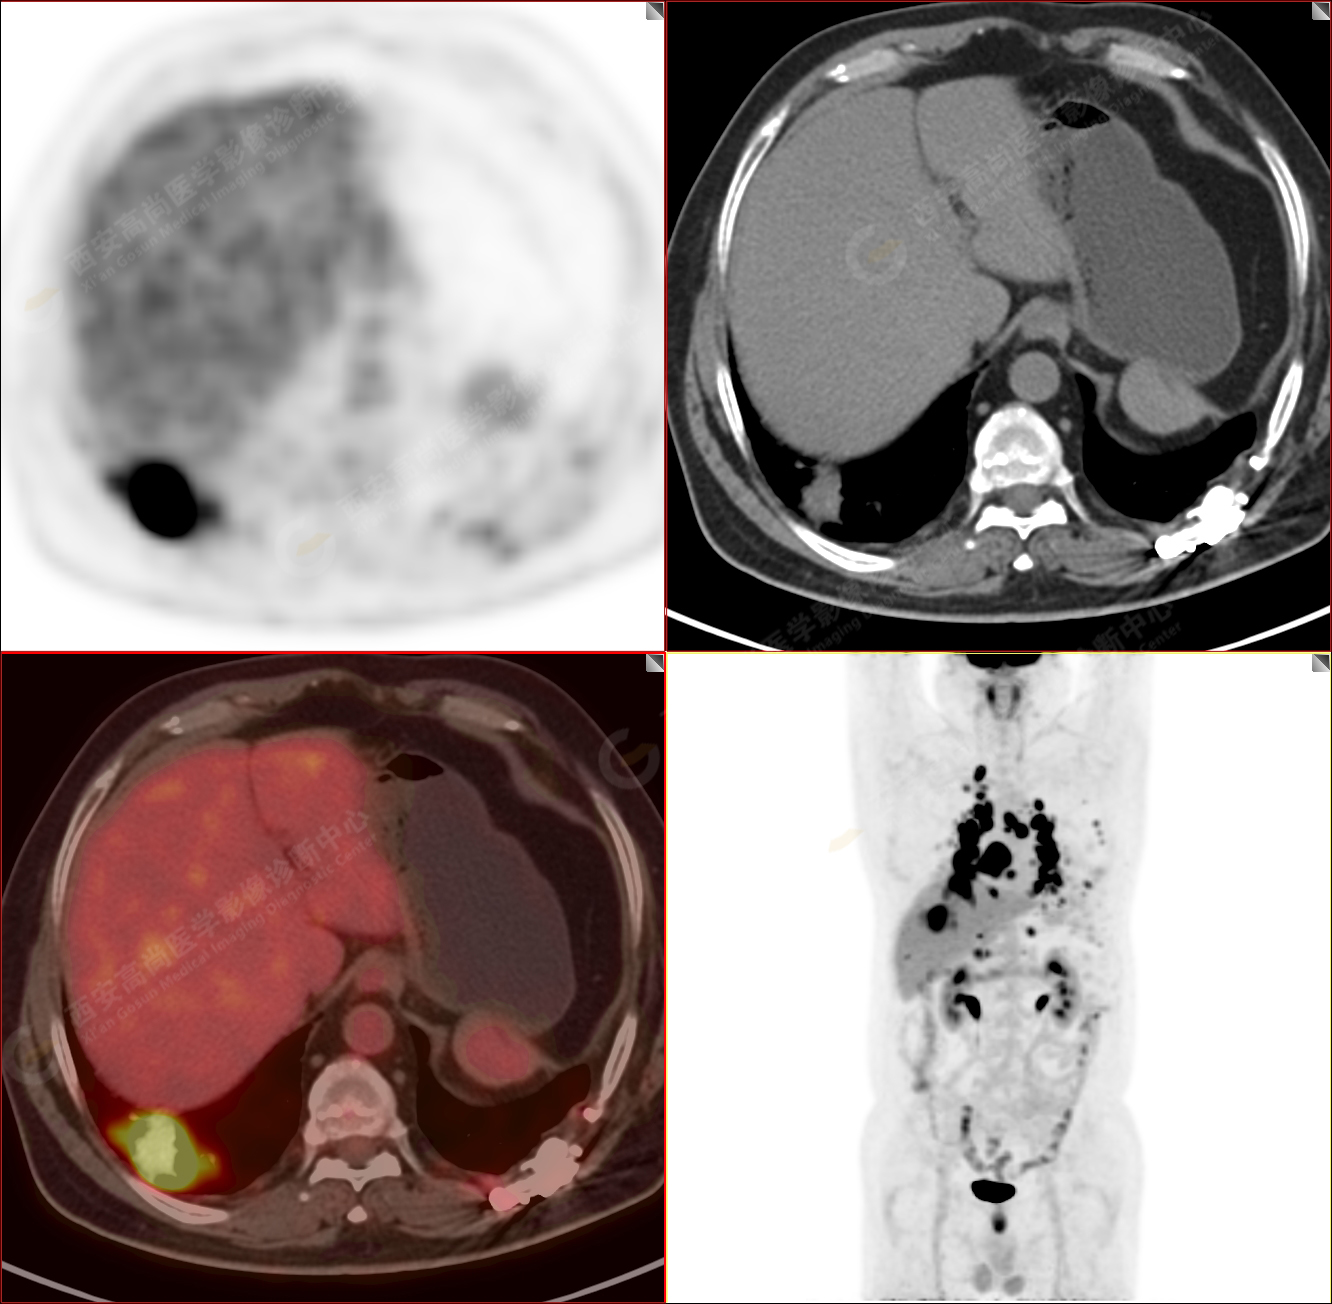

PET/CT圖像